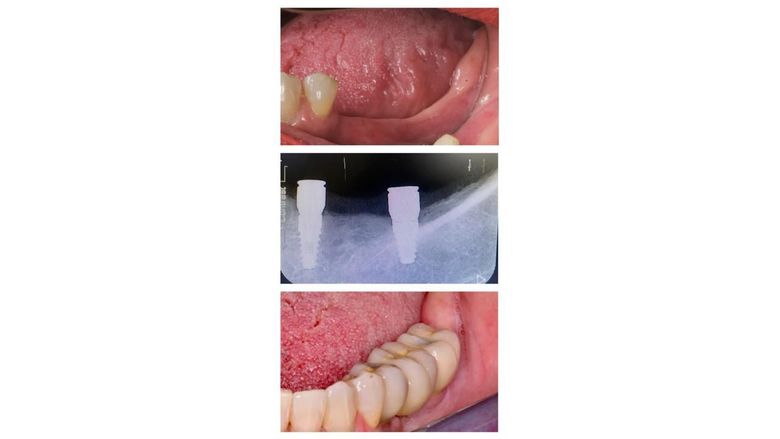

Prótesis sobre implantes

Unitarios, puentes y prótesis completas sobre implantes.